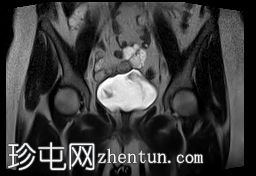

冠状位

T2加权像

MRI特征符合剖宫产术后瘢痕子宫内膜异位症,表现为特征性T1高信号伴T1FS持续存在,T2低信号伴内部高信号灶,病灶边缘浸润于腹前壁肌肉内,以及对比增强。

该病灶累及腹白线并浸润腹直肌,主要位于中线左侧,耻骨联合及结节处腹直肌起点上方。

影像学表现符合病灶内出血成分,提示既往剖宫产瘢痕处存在异位子宫内膜组织。

子宫可见剖宫产瘢痕灶。